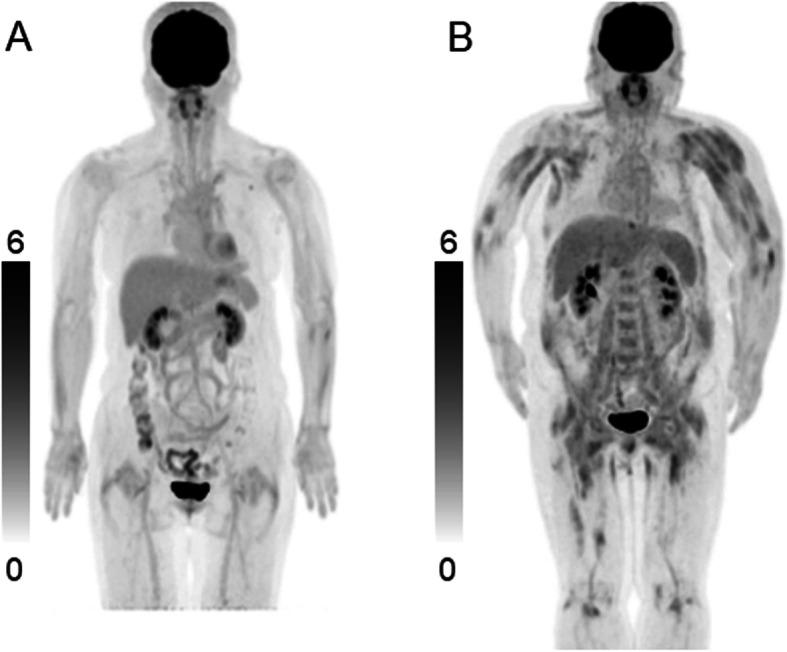

A total of 28 patients with untreated PM/DM and 28 control patients with non-muscular diseases were examined with F-FDG PET/CT. F-FDG uptake was evaluated in 9 proximal skeletal muscle regions bilaterally. The uptake was scored as follows: 0 = less than that of the mediastinal blood vessels, 1 = greater than or equal to that of the mediastinal blood vessels, and 2 = greater than or equal to that of the liver. A score 1 or 2 was considered positive. The mean and maximum standardized uptake values (SUV) were calculated in each muscle and were averaged for all muscle regions. PET findings were correlated with serum muscle enzymes.

F-FDG uptake was observed in 82% of patients with PM/DM and 7% of control patients. The number of positive regions, total score, mean SUVmean, and mean SUVmax in patients with PM/DM were significantly higher than those in the control patients (all P < 0.001). The total score of 2 was the best cut-off value that could discriminate patients with PM/DM from control patients. The total score, mean SUVmean, and mean SUVmax showed significant correlations with creatine kinase (P = 0.047, 0.002, 0.010, respectively) and aldolase (P = 0.036, 0.005, 0.038, respectively).

F-FDG PET/CT using visual and SUV methods demonstrated its usefulness by discriminating PM/DM from non-muscular diseases and correlating with serum muscle enzymes in patients with PM/DM.